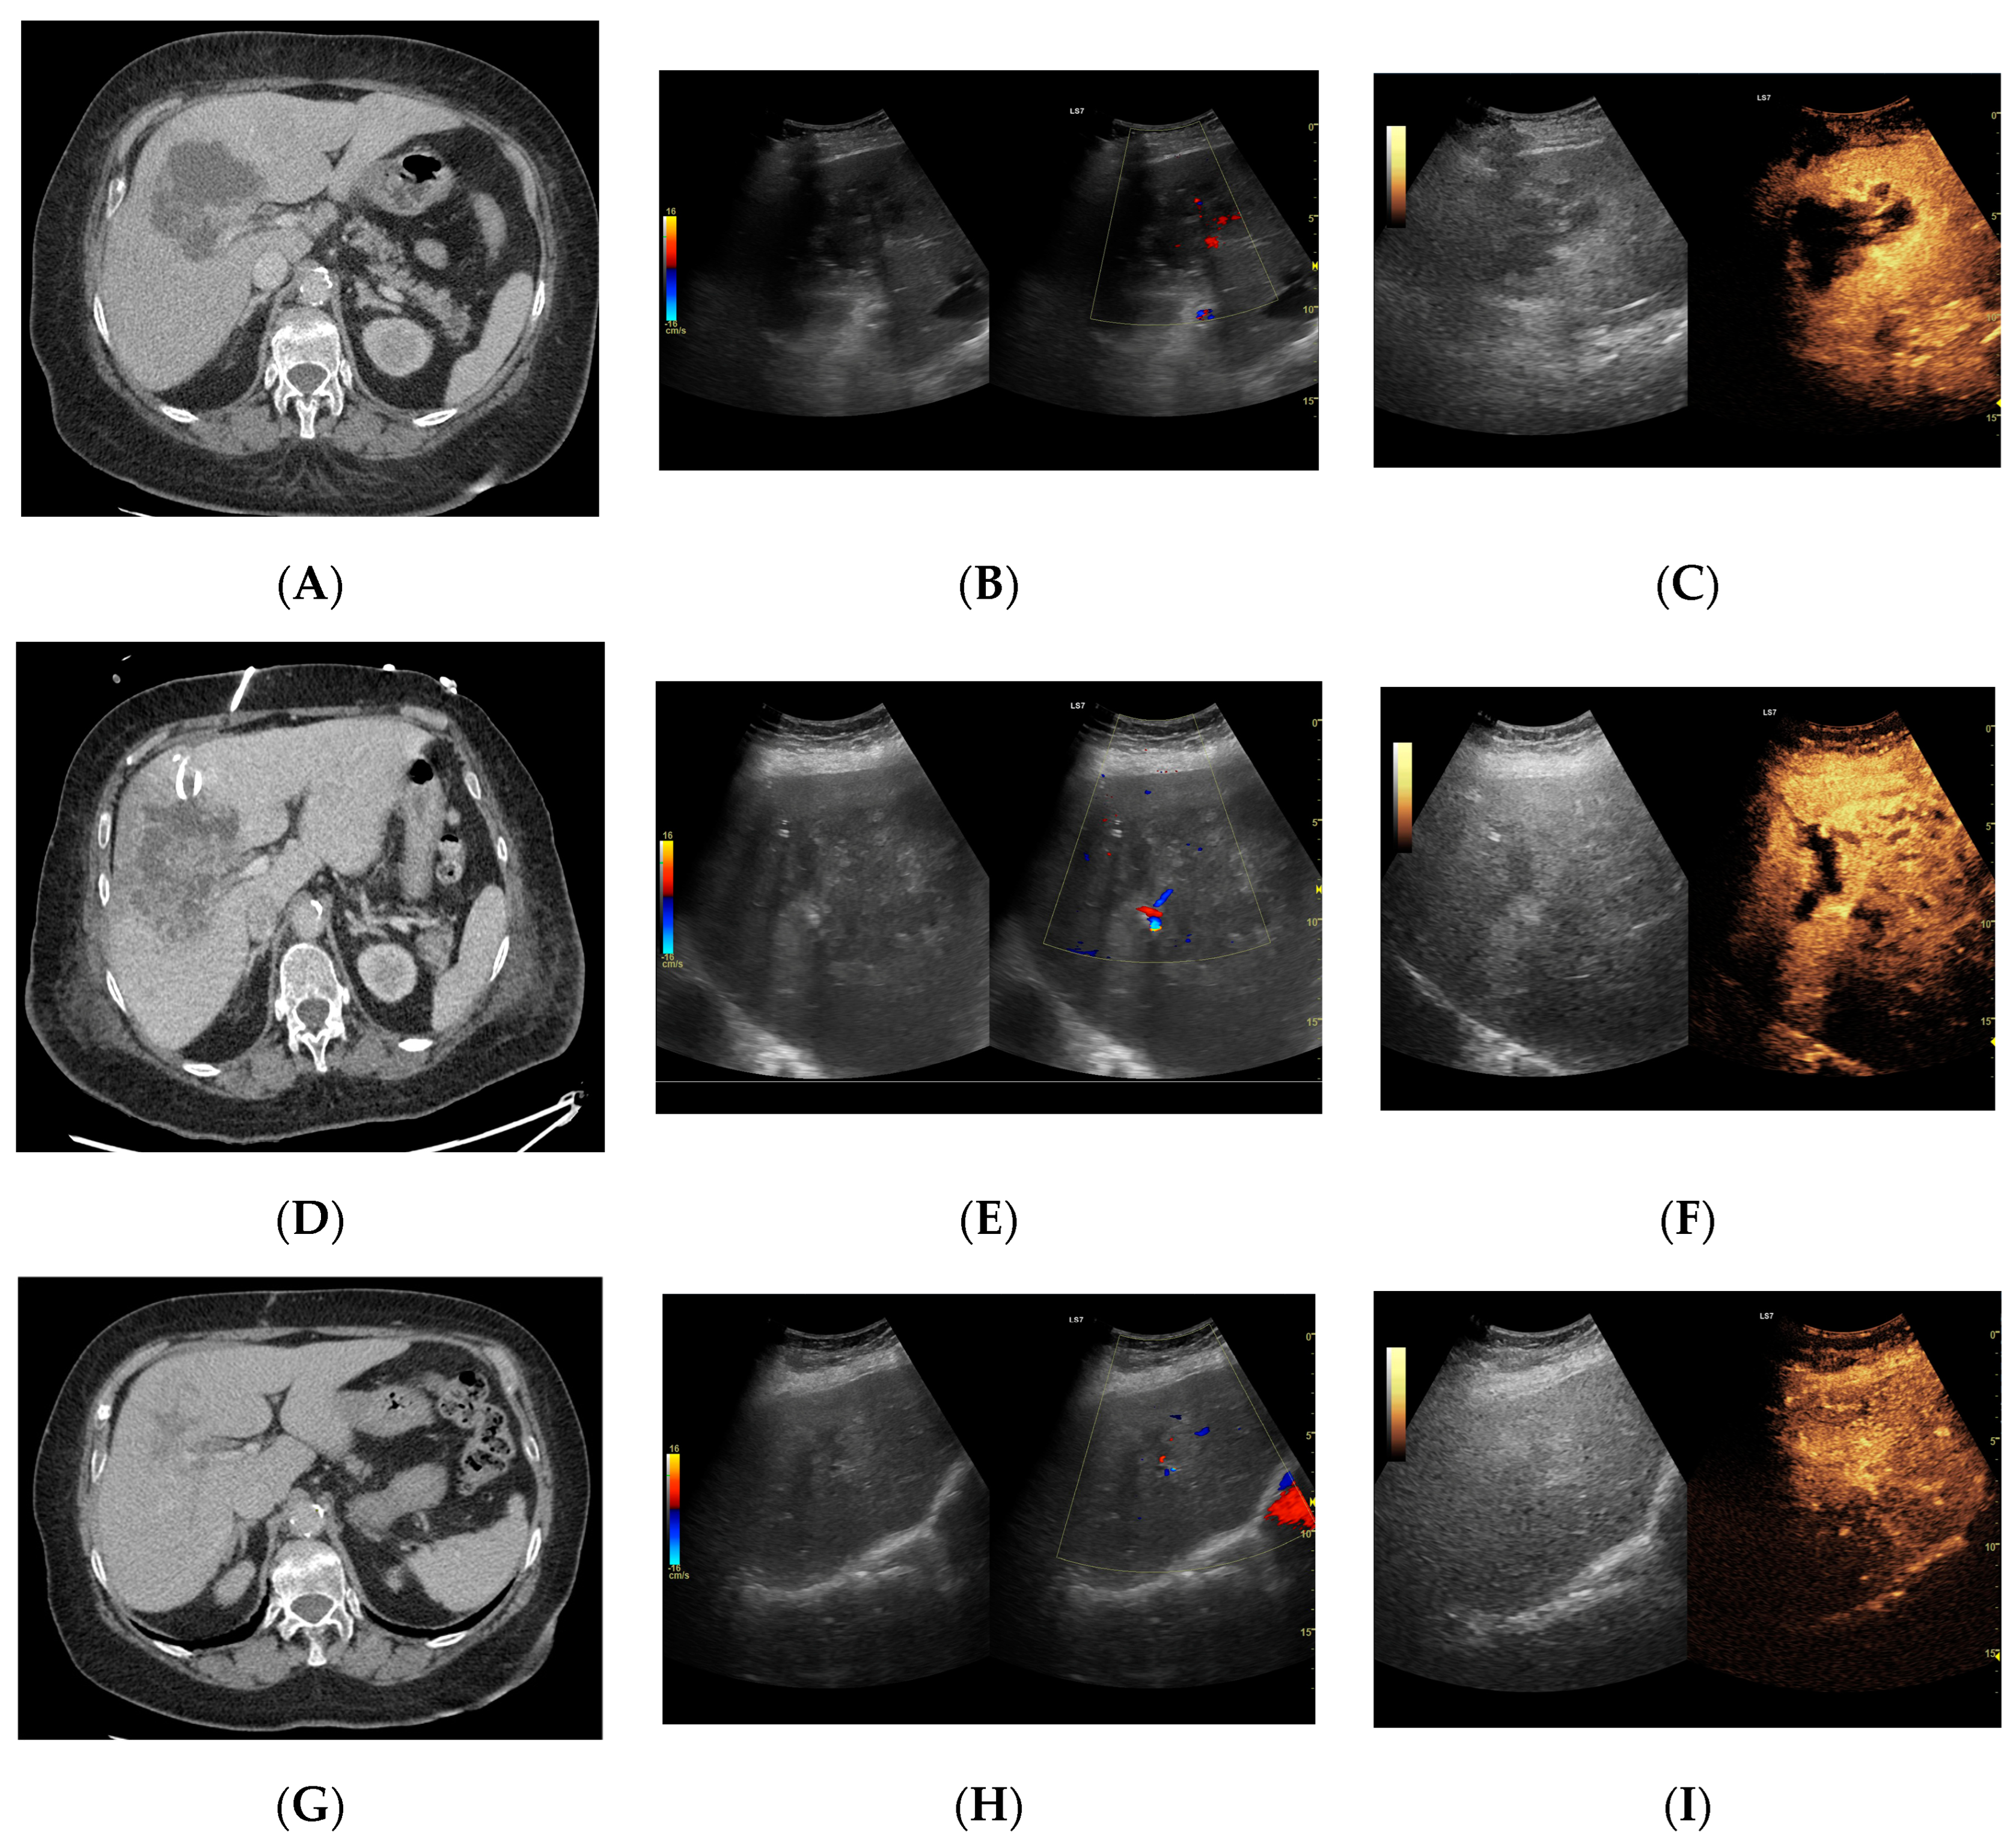

Since the difference in enhancement between the fluid component of HAs and their capsules was statistically significant throughout the study period, a morphological classification of HAs was performed. Additionally, the lesions were categorized based on their size, >6 cm (53 lesions) or <6 cm (59 lesions), and their volume, either >113 mL or <113 mL. Both CEUS and B-mode were consistent in determining the dimensions of HA, but they significantly differed in assessing the volume of the fluid component (Figure 3, Figure 4, Figure 5 and Figure 6).

Figure 3.

(A) Ultrasound and color Doppler: The transverse view shows a focal lesion involving virtually the entire liver parenchyma, identified as a type I abscess. In B-mode, the lesion appears solid and heterogeneous, with small hypoechogenic foci that can be identified as fluid fragments. Confident classification of the lesion as a hepatic abscess based on these images alone is impossible, including accurate determination of the content and location of the fluid component. (B) CEUS arterial phase: The enhanced abscess capsule is clearly visible, with the purulent content occupying virtually the entire lesion. There is the possibility to assess the liquefied component of the abscess with high accuracy. The total abscess was estimated to be 191.25 cm² from CEUS, while the fluid fractions were estimated at 6.51 cm² on B-mode and 166.51 cm² on CEUS, respectively, which, according to the methodology used, translates to 104.42 mL in B-mode and 2670.82 mL in CEUS, respectively. The enhancement of the abscess capsule is barely visible but similar to that of the parenchyma.

Figure 4.

(A) Ultrasound and color Doppler: The transverse view shows a focal lesion in the right liver lobe, identified as type II—honeycomb. In B-mode, the lesion appears solid and heterogeneous, surrounded by a hyperechoic capsule. Confident classification of the lesion as a hepatic abscess based on these images alone is impossible, including accurate determination of the content and location of the fluid component. (B) CEUS arterial phase: The enhanced abscess capsule is visible, with the lesion being heterogeneously contrasted and hyperdense in relation to the liver parenchyma. Hypodense fluid areas corresponding to pus are also visible. The total abscess was estimated to be 40.71 cm² from CEUS, while the fluid fractions were estimated at 0.44 cm² on B-mode and 6.17 cm² on CEUS, respectively, which, according to the methodology used, translates to 3.23 mL in B-mode and 45.35 mL in CEUS, respectively. The enhancement of the abscess capsule is similar to that of the parenchyma, and the greatest phase of inflammatory activity has passed, indicating that the lesion is in the resolution phase of inflammation.

Figure 5.

(A) Ultrasound and color Doppler: The transverse view shows a focal lesion in the right liver lobe, identified as a type III–, lacunar abscess, with visible septa in B-mode. In this case, it is possible to clearly classify the lesion as a type III abscess and determine its actual fluid component. (B) CEUS arterial phase: The enhanced abscess capsule and septa are visible. The total abscess was estimated to be 124.16 cm² from CEUS, while the fluid fractions were estimated at 57.43 cm² on B-mode and 61.55 cm² on CEUS, respectively, which, according to the methodology used, translates to 914.86 mL in B-mode and 980.49 mL in CEUS, respectively. The enhancement of the abscess capsule is slightly higher than that of the parenchyma. The lesion remains in the active phase of inflammation, although with less intensity.

Figure 6.

(A) Ultrasound and color Doppler: The transverse view shows a focal lesion in the right liver lobe, identified as a type IV–, a cystic–like abscess, with a visible capsule in B-mode. In this case, it is possible to clearly classify the lesion as a type IV abscess and determine its actual fluid component. (B) CEUS arterial phase: The enhanced abscess capsule is visible. The total abscess was estimated to be 25.95 cm² from CEUS. The fluid component in CEUS overlaps with the B-mode image and measures 16.15 cm², so the volume is the same in both cases at 102.71 mL. The enhancement of the abscess capsule is slightly higher than that of the parenchyma. The lesion remains in the active phase of inflammation, although with less intensity.